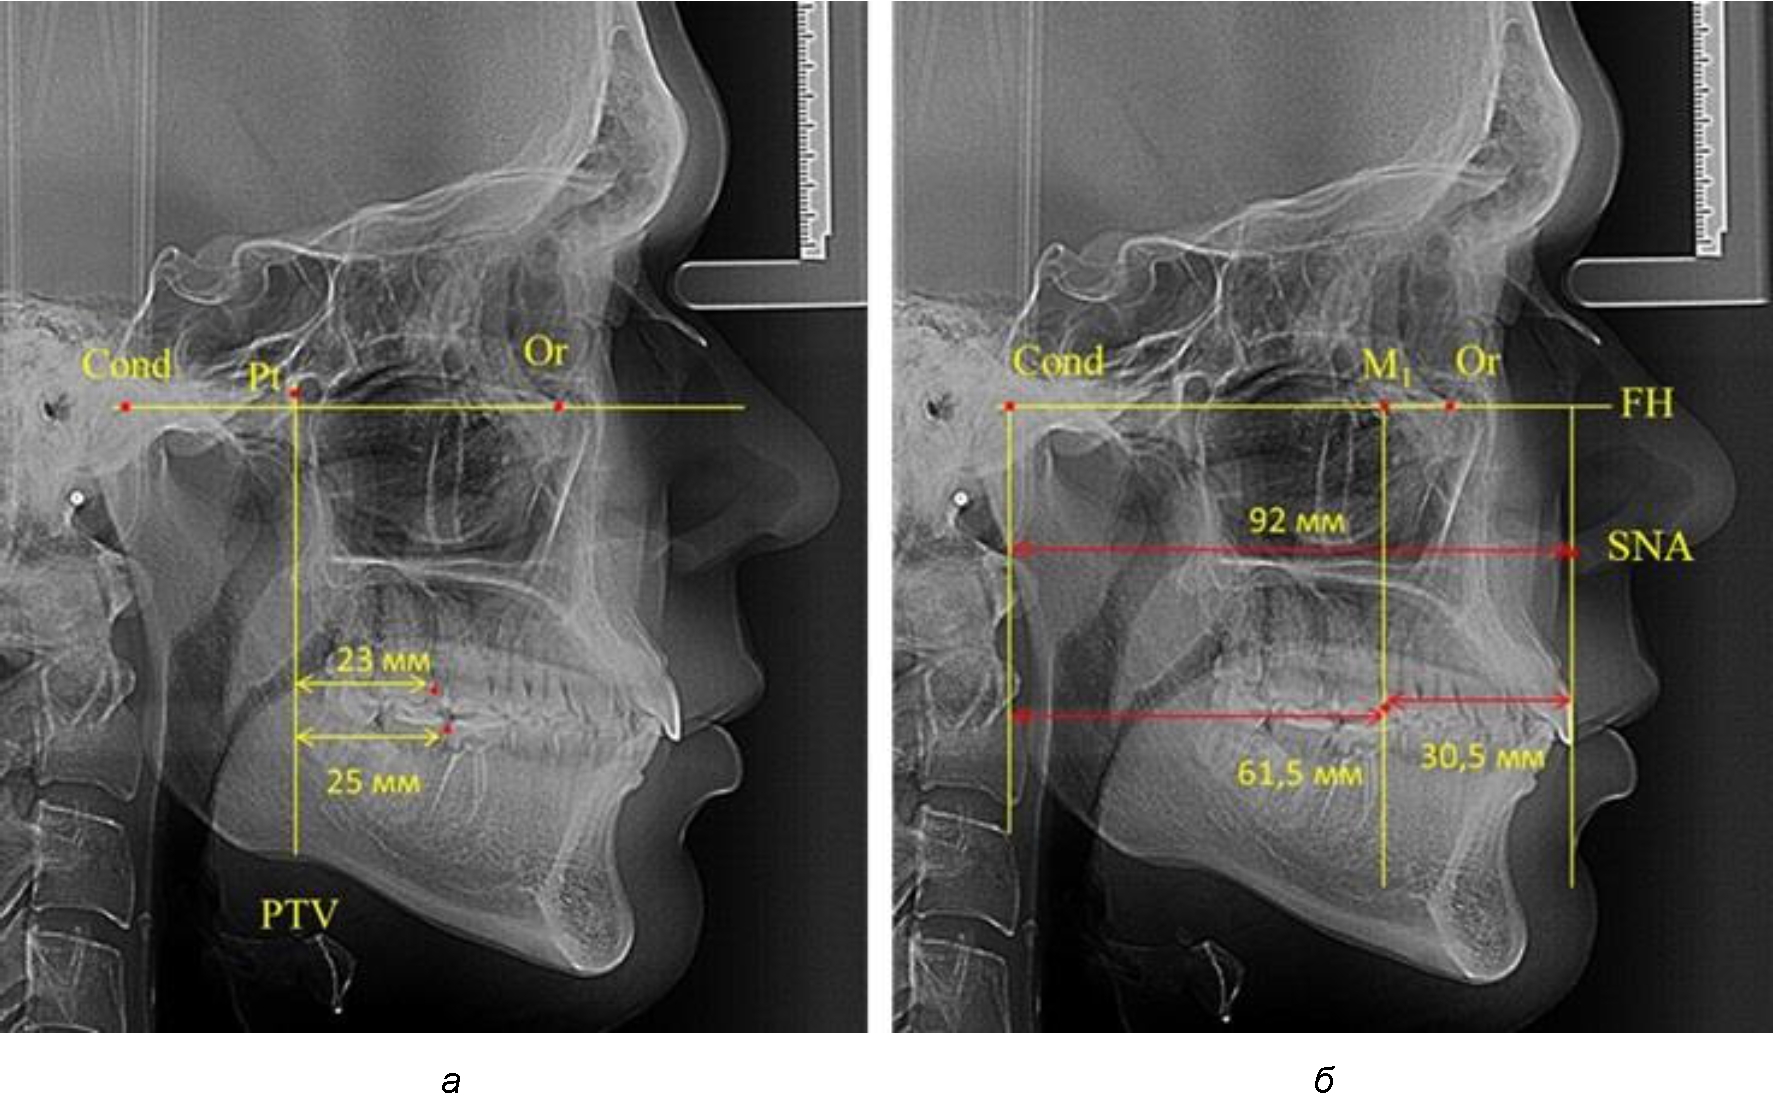

При проведении анализа к Франкфуртской горизонтали проводили передний и задний перпендикуляры. Передний спинальный перпендикуляр проходил через выступающую точку передней носовой ости (spina nasalis anterior – SNA), а задний суставной перпендикуляр опускали из кондилярной точки Cond. Молярный перпендикуляр проводили через медиальную поверхность первого постоянного моляра. Указанная вертикаль отделяла замещающие зубы постоянного прикуса от добавочных зубов (постоянных моляров), что вполне логично для анализа положения первых постоянных моляров в гнатическом комплексе (рис. 1).

Рис. 1. Метод определения положения первых верхних моляров по Ralph E. McDonald (а) и по предложенному методу (б)

Анализ проведенного исследования рентгенограмм показал существенную вариабельность практически всех линейных показателей. У молодых людей с физиологическим прикусом постоянных зубов расстояние от крыловидной вертикальной плоскости PTV до дистальной поверхности верхнего первого постоянного моляра в целом по группе составляло (18,37 ± 3,62) мм. Обращает на себя внимание большая ошибка репрезентативности из-за разницы между максимальными и минимальными значениями.

Среди анализируемых рентгенограмм минимальное значение расстояния по методу R. E. McDonald было 12 мм, а максимальное достигало 25 мм, что, по нашему мнению, обусловлено вариабельностью сагиттального размера гнатического отдела лица.

Среднее расстояние между суставной (кондилярной) и спинальной вертикалями в анализируемой группе составило (89,12 ± 2,8) мм. При этом сагиттальный размер в среднем составлял (58,74 ± 1,57) мм, а передний размер был (30,41 ± 1,02) мм. Несмотря на вариабельность размеров и большую ошибку репрезентативности, относительно стабильным показателем было отношение сагиттального размера гнатического комплекса к заднему отделу, которое составляло в среднем 1,5 ± 0,06.

Таким образом, для прогнозирования оптимального положения первых постоянных моляров наиболее целесообразным методом явилось использование относительного показателя, что подтверждено при анализе рентгенограмм с минимальными и максимальными значениями по методу R. E. McDonald.

В то же время при увеличенном расстоянии от крыловидной вертикальной плоскости PTV до дистальной поверхности верхнего первого постоянного моляра, равное 23 мм, сагиттальный размер гнатического отдела составил 92 мм. При этом отношение кондилярно-спинального расстояния к кондилярно-молярному размеру (30,5), так же, как и при малых размерах, было близким к коэффициенту 1,5, что представлено на рис. 3.